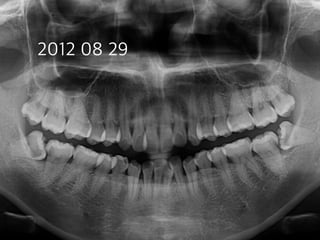

#31 partial pulpotomy

follow-up

(38 female)

2005 03 19 2005 09 28

2007 07 31 48m later

2012 08 29

2012 11 22

14m later

16m later